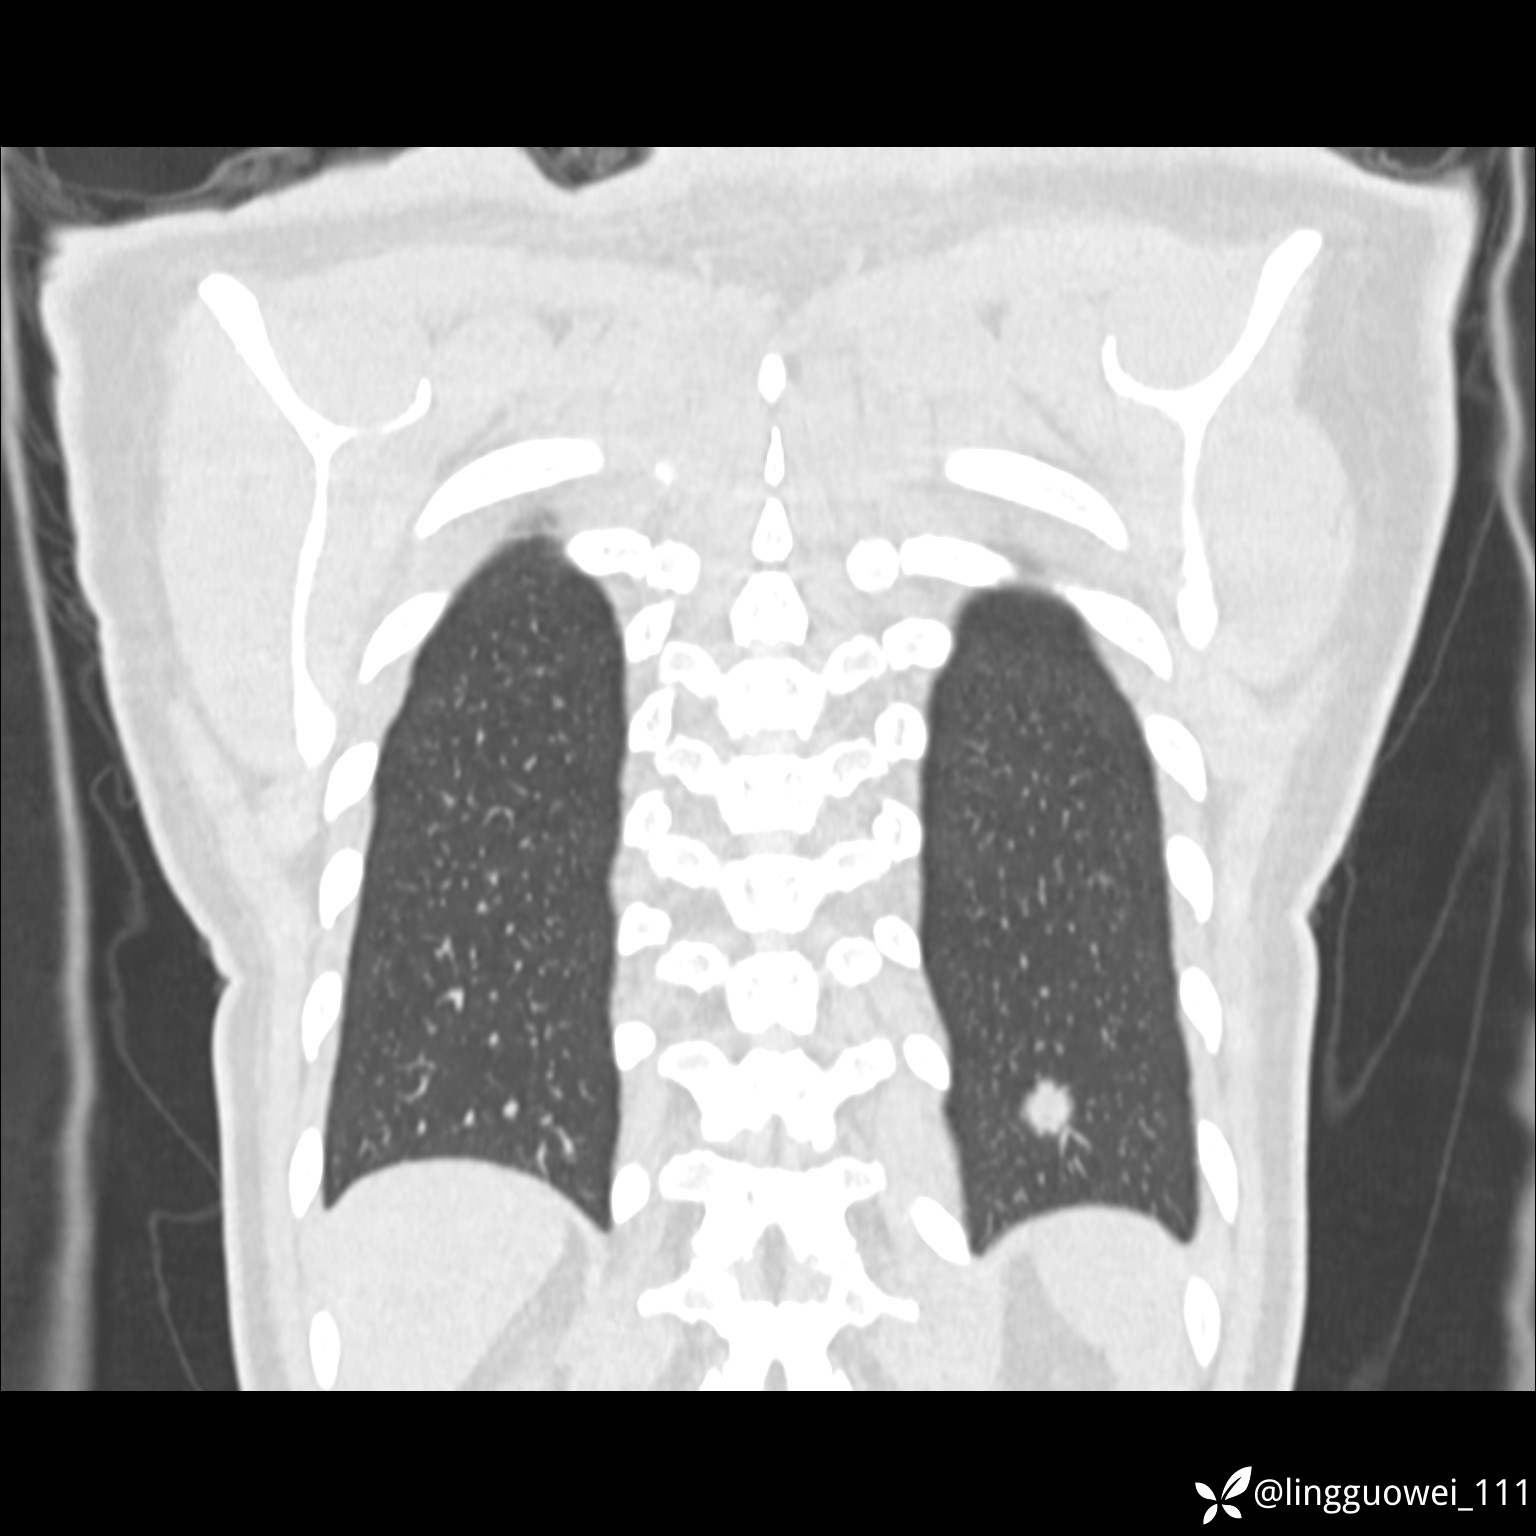

患者性别:女

患者年龄:26岁

主诉:咳嗽来诊,结节性质不明。

肺毛细血管瘤 (2)